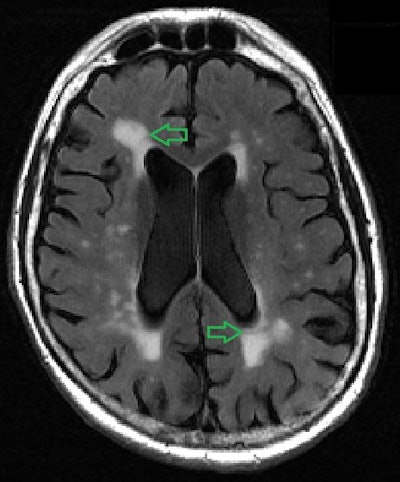

The algorithm suggests a better way to assess small bright spots on MRI called white-matter hyperintensities, according to a team led by senior author Dr. Yulin Ge of NYU Langone Health in New York City. The spots are fluid-filled holes in the brain that develop from the breakdown of the blood vessels that support nerve cells and are linked to memory loss and emotional problems as people age.

White-matter hyperintensities are easily imaged on MRI, but their origin and pathophysiology aren't always clear, the group noted. Typically, radiologists assess these lesions based on visual interpretation and a three-point scale. The new calculator offers an objective way to evaluate the volume and location of the lesions, according to the researchers.